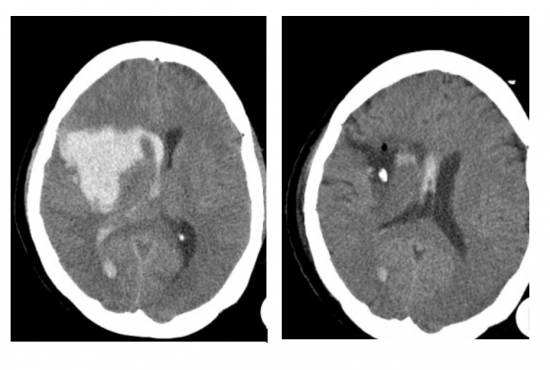

Η εγκεφαλική αιμορραγία είναι μια επείγουσα κατάσταση και απαιτεί άμεση διάγνωση. Η αξονική τομογραφία είναι η πιο σημαντική εξέταση γιατί μπορεί με βεβαιότητα να βάλει ή να αποκλείσει τη διάγνωση της εγκεφαλικής αιμορραγίας. Δίνει επίσης πληροφορίες για το μέγεθος και τη θέση της αιμορραγίας, για την παρουσία ενδοκοιλιακής αιμορραγία (δηλαδή αίματος εντός των κοιλιών του εγκεφάλου), την παρουσία οιδήματος, αν υπάρχει παρεκτόπιση των δομών της μέσης γραμμής κ.ο.κ.

Οίδημα γύρω απο το αιμάτωμα παρατηρείται στην αξονική (CT) ή μαγνητική τομογραφία (MRI) σε τουλάχιστον τους μισούς ασθενείς. Το οίδημα αυτό εξελίσσεται, δηλαδή προχωρά, φτάνοντας τον μέγιστο όγκο 7 έως 12 ημέρες μετά την έναρξη της αιμορραγίας. Μάλιστα, η πιο γρήγορη επέκταση του οιδήματος συμβαίνει τις πρώτες 48 ώρες.

Το αιμάτωμα το ίδιο συχνά επίσης μεγαλώνει. Μελέτες έχουν δείξει ότι τα αιματώματα αυξάνονται τις πρώτες 3 ώρες. Σε μια μελέτη 103 ασθενών με εγκεφαλική αιμορραγία, διαπιστώθηκε ότι το 38% των ασθενών παρουσίασαν σημαντική αύξηση της εγκεφαλικής τους αιμορραγίας εντός 24 ωρών.